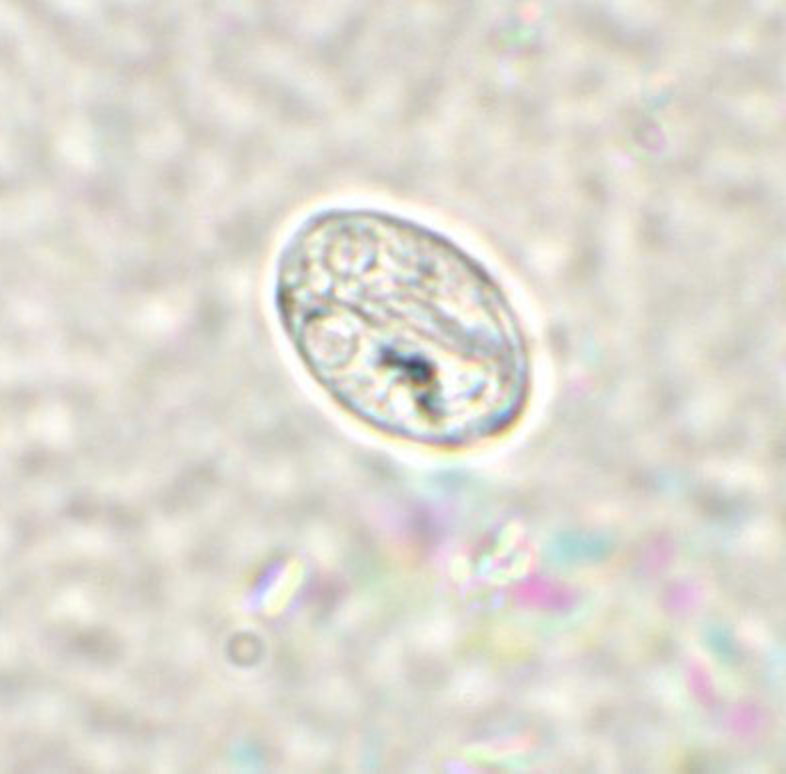

Giardia lamblia cyst